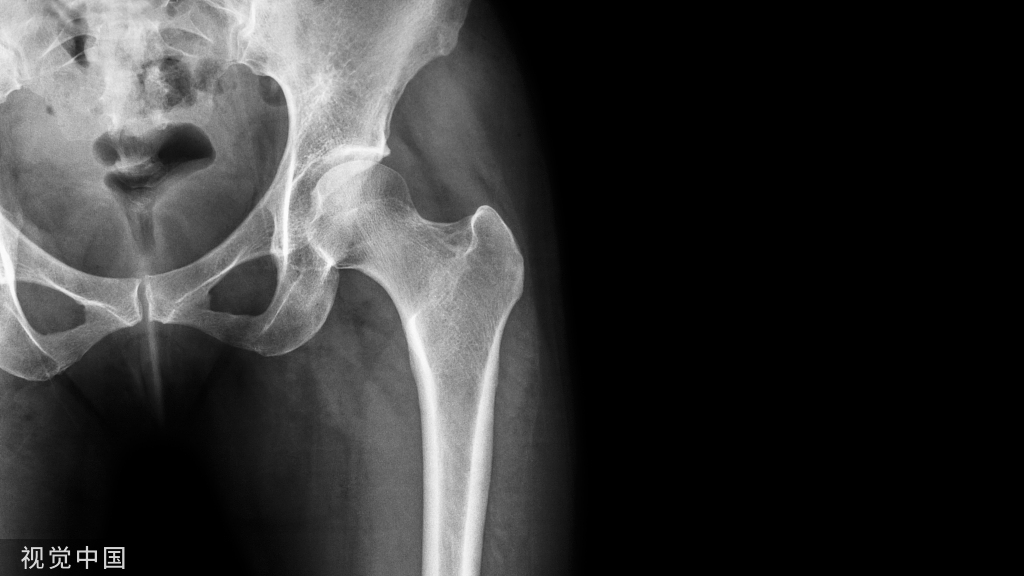

股骨头坏死发展过程中,X线片上出现“新月”征时,意味着股骨头已经开始塌陷。

所谓股骨头新月征,是指股骨头(前外侧多见)软骨下骨板的下方出现空腔,X线片上(通常为蛙位X线片)表现为2~4mm宽的新月形透明带,类似一轮新月,故名"新月征(crescent sign)"。